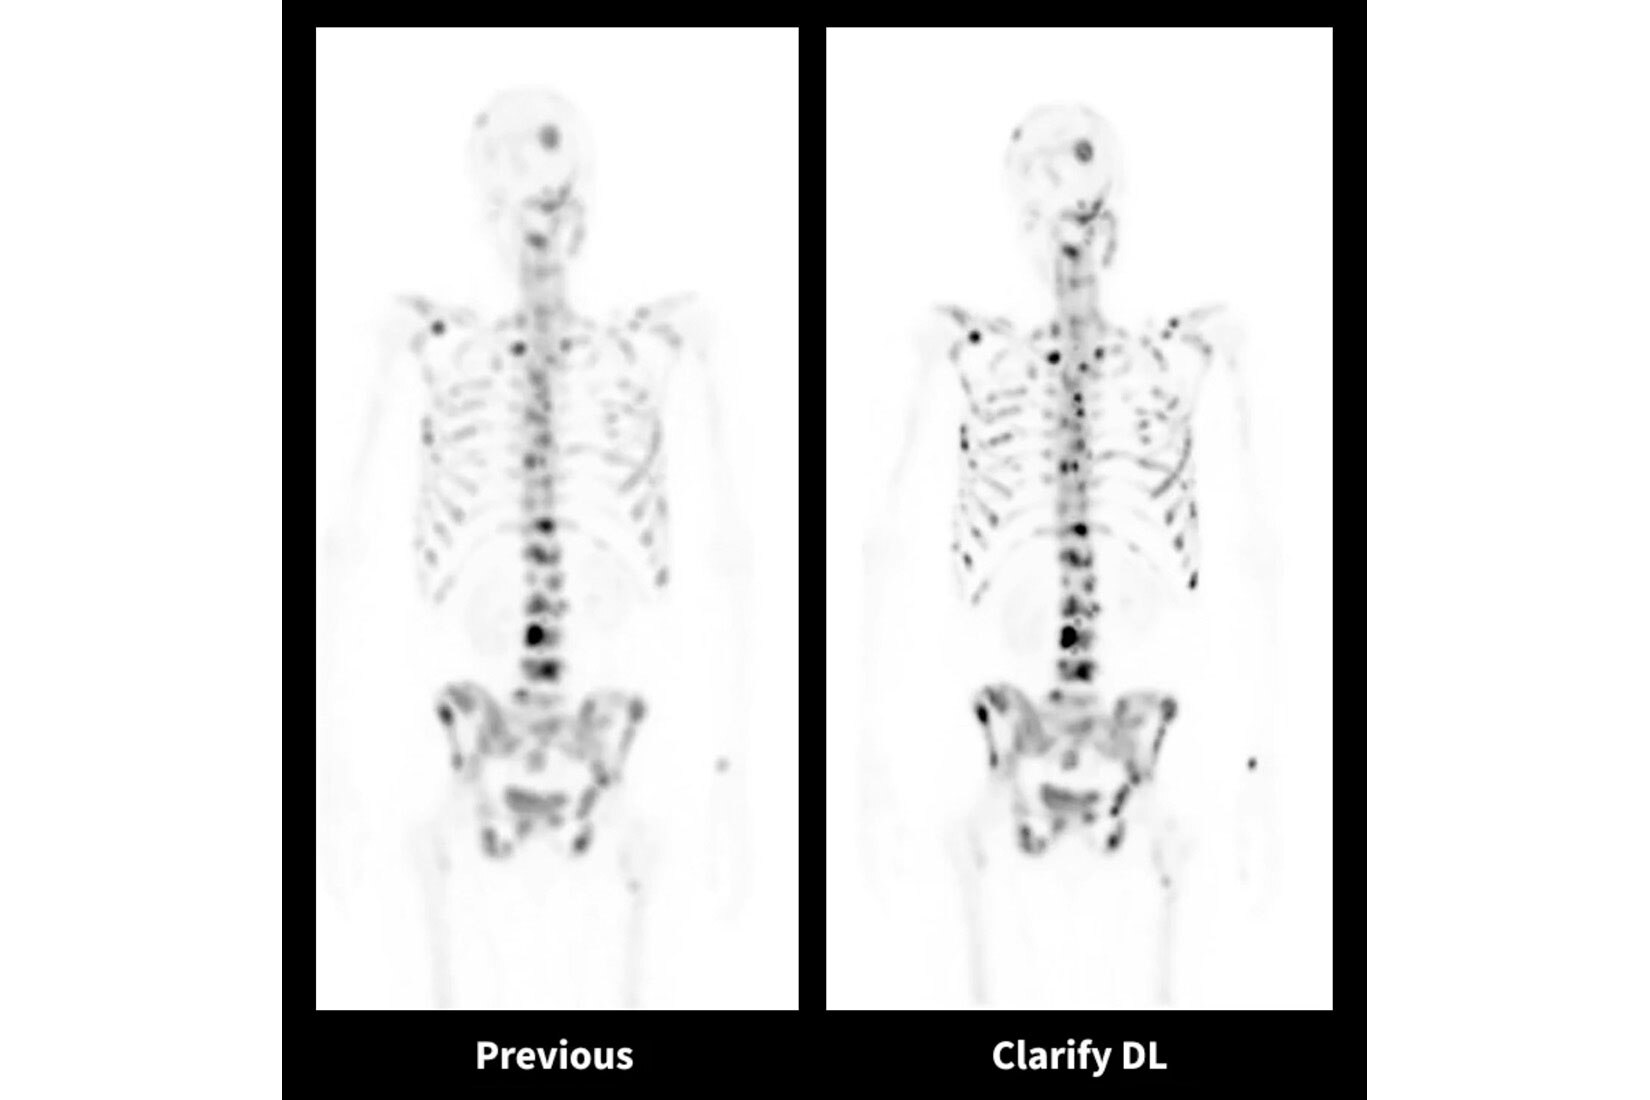

AIR™ Recon DL

AIR™ Recon DL potenzia le funzionalità della tua RM offrendo una qualità dell'immagine superiore con tempi di scansione ridotti.